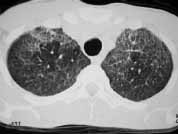

En la radiografía de tórax se evidenciaron infiltrados de ocupación alveolar en parche de distribución periférica. El ecocardiograma mostró miocardiopatía dilatada en fase leve y signos indirectos de hipertensión pulmonar.

Además del antecedente de inyección subcutánea de silicona, y teniendo en cuenta su mayor relación con múltiples inyecciones y mayor cantidad de sustancia, el hallazgo radiológico de infiltrados alveolares periféricos que afectan principalmente la corteza pulmonar es muy sugestivo de embolismo de esta sustancia.

Ante la presencia de edema pulmonar de permeabilidad o hemorragia alveolar estos infiltrados pueden hacerse difusos. La TACAR resalta este hallazgo, y se suma la presencia de engrosamiento de líneas septales probablemente relacionadas con diseminación linfática de silicona.

Figura 5. TACAR: Demuestra la presencia de áreas de vidrio esmerilado difuso e infiltrados alveolares en parches, secundarios a hemorragia alveolar y embolismo por silicona.